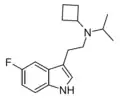

| 5-Fluoro-DMT | artificial | 5-F | CH3 | CH3 | 5-fluoro-N,N-dimethyltryptamine | 22120-36-1 |

| 5-Fluoro-MET | artificial | 5-F | CH3 | CH2CH3 | 5-fluoro-N-methyl-N-ethyltryptamine | |

| 5-Fluoro-DET | artificial | 5-F | CH2CH3 | CH2CH3 | 5-fluoro-N,N-diethyltryptamine | |

| 5-Fluoro-EPT | artificial | 5-F | CH2CH3 | CH2CH2CH3 | 5-fluoro-N-ethyl-N-propyltryptamine | |

| 5-Fluoro-DPT | artificial | 5-F | CH2CH2CH3 | CH2CH2CH3 | 5-fluoro-N,N-dipropyltryptamine | |

| 5-Fluoro-PiPT | artificial | 5-F | CH2CH2CH3 | CH(CH3)2 | 5-fluoro-N-propyl-N-isopropyltryptamine | |

| 5-Fluoro-PcBT | artificial | 5-F | CH2CH2CH3 | CH(CH2)3 | 5-fluoro-N-propyl-N-cyclobutyltryptamine | |

| 5-Fluoro-iPcBT | artificial | 5-F | CH(CH3)2 | CH(CH2)3 | 5-fluoro-N-isopropyl-N-cyclobutyltryptamine | |

| 5-Fluoro-DiPT | artificial | 5-F | CH(CH3)2 | CH(CH3)2 | 5-fluoro-N,N-diisoproptryptamine | |

| 5-Fluoro-sBALT | artificial | 5-F | CH(CH3)CH2CH3 | CH2CH=CH2 | 5-fluoro-N-sec-butyl-N-allyltryptamine | |

| 5-Fluoro-M1MALT | artificial | 5-F | CH3 | CH(CH3)CH=CH2 | 5-fluoro-N-methyl-N-(1-methylallyl)tryptamine | |